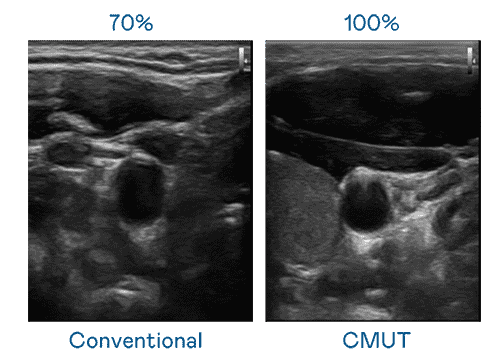

CMUT 技术是一种用电容式微机电元件来产生超音波讯号的技术。。。与传统 PZT 压电式技术相比,,CMUT 频宽增加 30%,,,,更宽频的超音波讯号让影像解析度大幅提升,,,是实现高影像品质医疗超音波扫描、、、促进精准医疗发展的关键技术。。。

大频宽带来超清晰影像

超音波影像的解析度高低,,,,首先取决于探头能发出的讯号频宽。。。蓝狮在线 CMUT 可提供高清晰的超音波讯号,,,提供高频宽、、、高灵敏度、、影像纹理细节更高的超音波影像,,,协助医护人员缩短影像判读时间及利用精准的医疗影像进行诊断。。。。